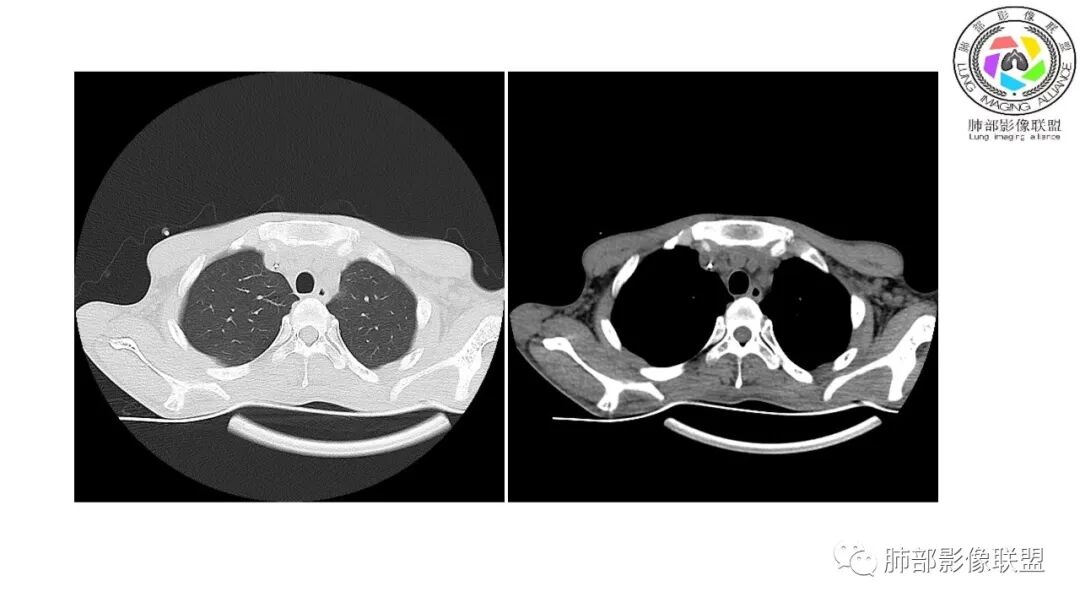

影像与临床:1.青年男性,HlV阳性,颜面部皮疹(未提供皮疹图像)、发热(高热),实验室CRP、PCT高,T-Spot阴性。2.右肺下叶空洞结节,壁厚不均,边界清楚,其内线状影,未见液平及钙化,未见卫星灶,纵隔淋巴结增大,双侧腋窝见增大淋巴结。心腔内低密度提示贫血可能。肝脾影增大,未见结节影及块影。腹膜后见多发增大淋巴结。

综合分析:本例肺部影像学改变并不具有特征性,空洞性病灶须与多种疾病鉴别,但年轻HIV阳性患者,高热,皮疹,肝脾增大,纵隔、腋窝、腹膜后见多发增大淋巴结等都强烈提示马尔尼菲篮状菌感染的可能性。